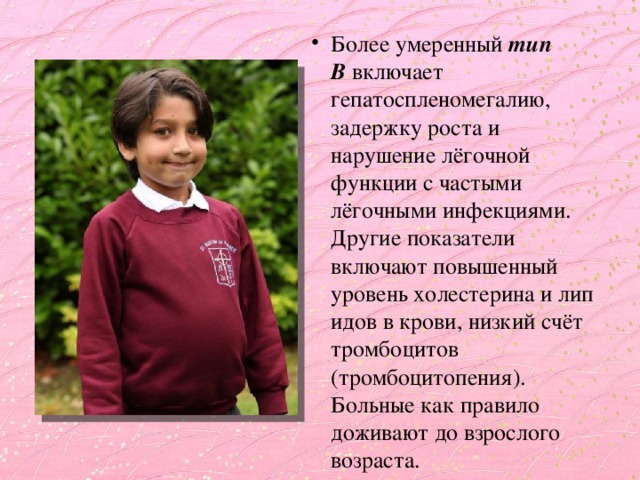

Болезнь Нимана-Пика Тип А: Симптомы и лечение